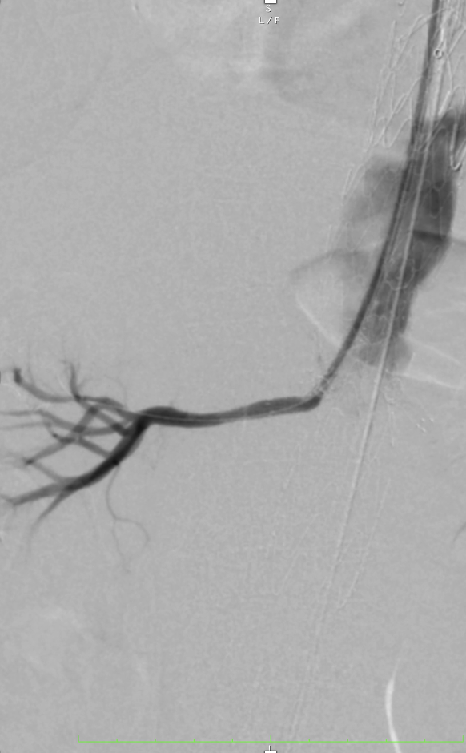

超选SMA,桥接8-100mm Viabahn,内衬8-60mm Absolute裸支架

超选CA,桥接8-100mm Viabahn

超选RRA烟囱支架,桥接6-100mm+6-50mm Viabahn

超选LRA烟囱支架,桥接6-100mm Viabahn

术后造影